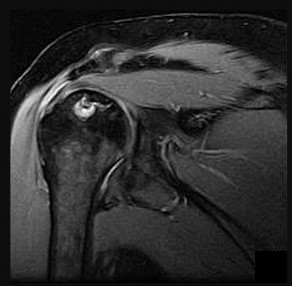

Question 7:

A 65-year-old man presents with progressive clumsiness in his hands, difficulty buttoning his shirt, and a broad-based gait. A T2-weighted MRI shows spinal cord compression with intrinsic cord signal change at C4-C5. Which of the following MRI findings is associated with the poorest prognosis for neurological recovery after surgical decompression in cervical spondylotic myelopathy?

Correct Answer: T1 hypointensity corresponding to the T2 hyperintensity

Explanation:

In cervical spondylotic myelopathy, the presence of T1 hypointensity corresponding to a T2 hyperintense lesion indicates myelomalacia or cystic necrosis of the spinal cord. This finding is a strong predictor of poor functional recovery following surgical decompression.